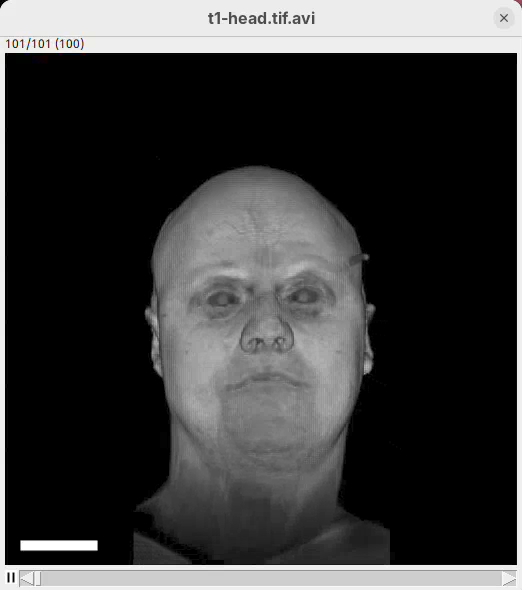

We will begin by visualizing an MRI dataset of a human head that is bundled in Fiji.

- Go to

File>Open Samples>T1 Head (16-bits).

- Increase the zoom to 200% for better visualization.

Orthogonal Views

Orthogonal Views is a tool that shows the optical sections through the orthogonal planes of XY: XZ and YZ. It is an easy and quick way to get a sense of the tridimensionality of your dataset. Whenever I’m opening a dataset for the first time I use Orthogonal Views. To activate it:

- Click on

Image>Stacks>Orthogonal Views(or pressCtrl+Shift+H). - The XZ and YZ panels will open next to your XY stack.

- The yellow lines are synchronized between the panels.

- Click around the different parts of the head to inspect the same position under different angles.

Orthogonal Views is a great way to start understanding your 3D data.